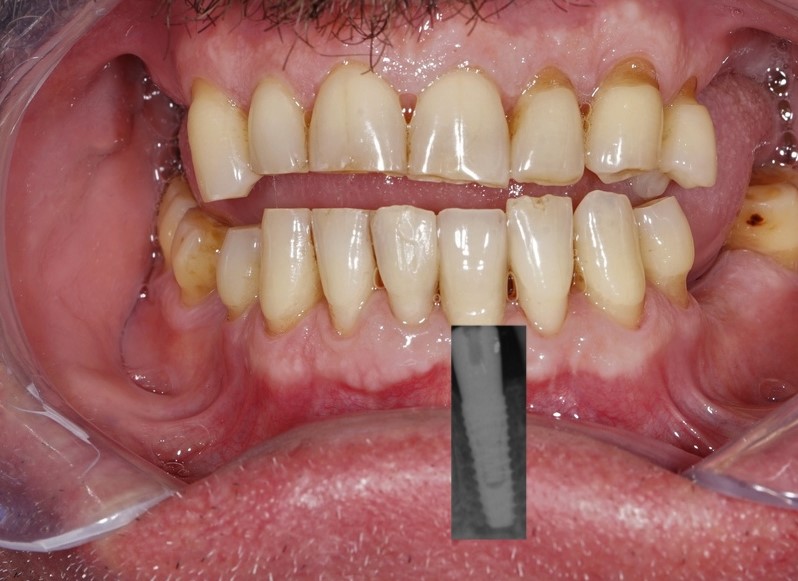

Implantul dentar reprezinta solutia optima din ce in ce mai mult practicata de tratament a lipsei unuia sau mai multor dinti. Fiecare caz de implant dentar sau interventie chirurgicala este initiat prin evaluarea starii generale de sanatate, examinarea clinica a zonei de interventie, examinarea radiologica prin radiografie conventionala si/sau tomografie computerizata speciala dento-maxilara, dar si fotografii clinice pentru analiza detaliata prechirurgical.